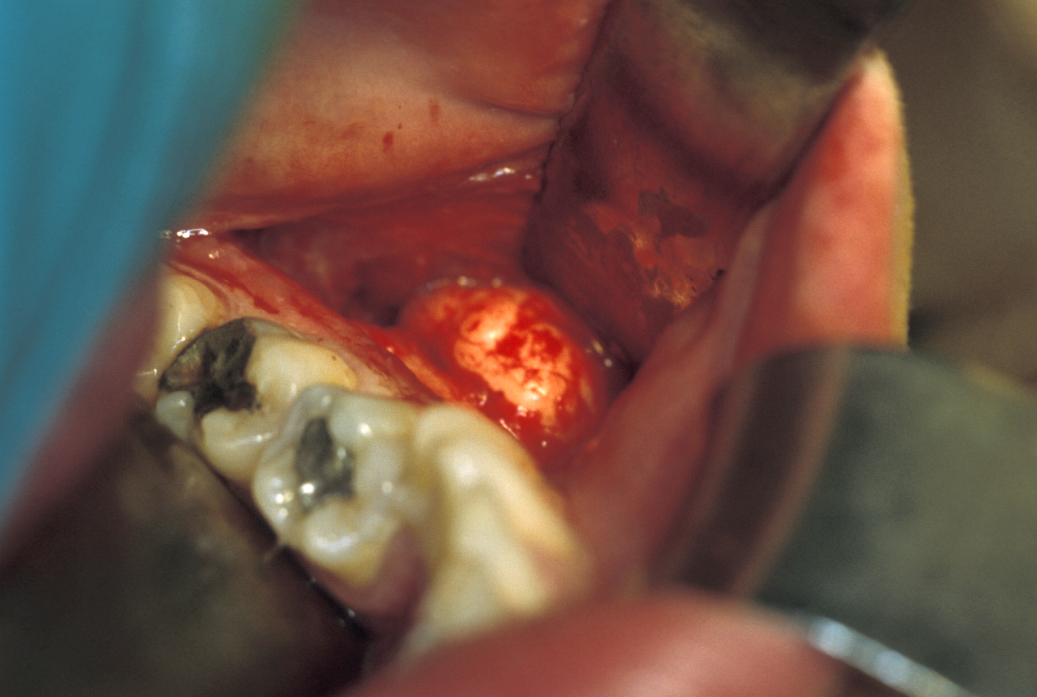

Treatment can be problematic. Long-term antibacterial therapy has been reported as being of benefit if given early in the course of the disease, but there are also reports that high-dose long-term antibacterial therapy has no beneficial effects. In more refractory cases, a course of corticosteroids and decortication may be of benefit. Hyperbaric oxygen therapy can be used to supplement the surgery although the evidence base is conflicting. Bisphosphonates have been advocated for chronic pain but have obvious conflicting risks regarding development of osteonecrosis. In some cases, more radical surgical intervention is required, such as resection of the affected region of the mandible (Figure 1 and Figure 2; note that the surgical techniques are essentially the same for some benign and malignant (see below) conditions).

Figure 1: Rim resection of sclerotic mandibular bone with dissection and preservation of the inferior alveolar and mental nerve (top); bone graft and reconstruction plates in place (bottom).